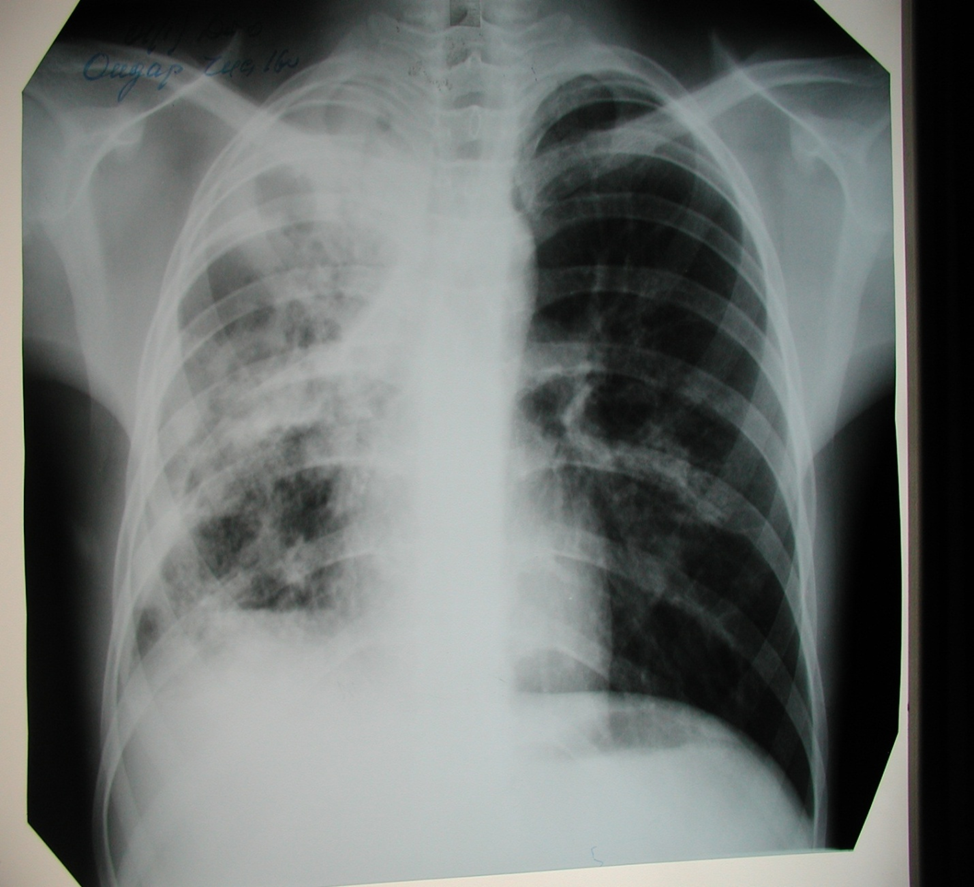

Симптомы и лечение инфильтративного туберкулеза легких

Раздел: Снимки-откровения